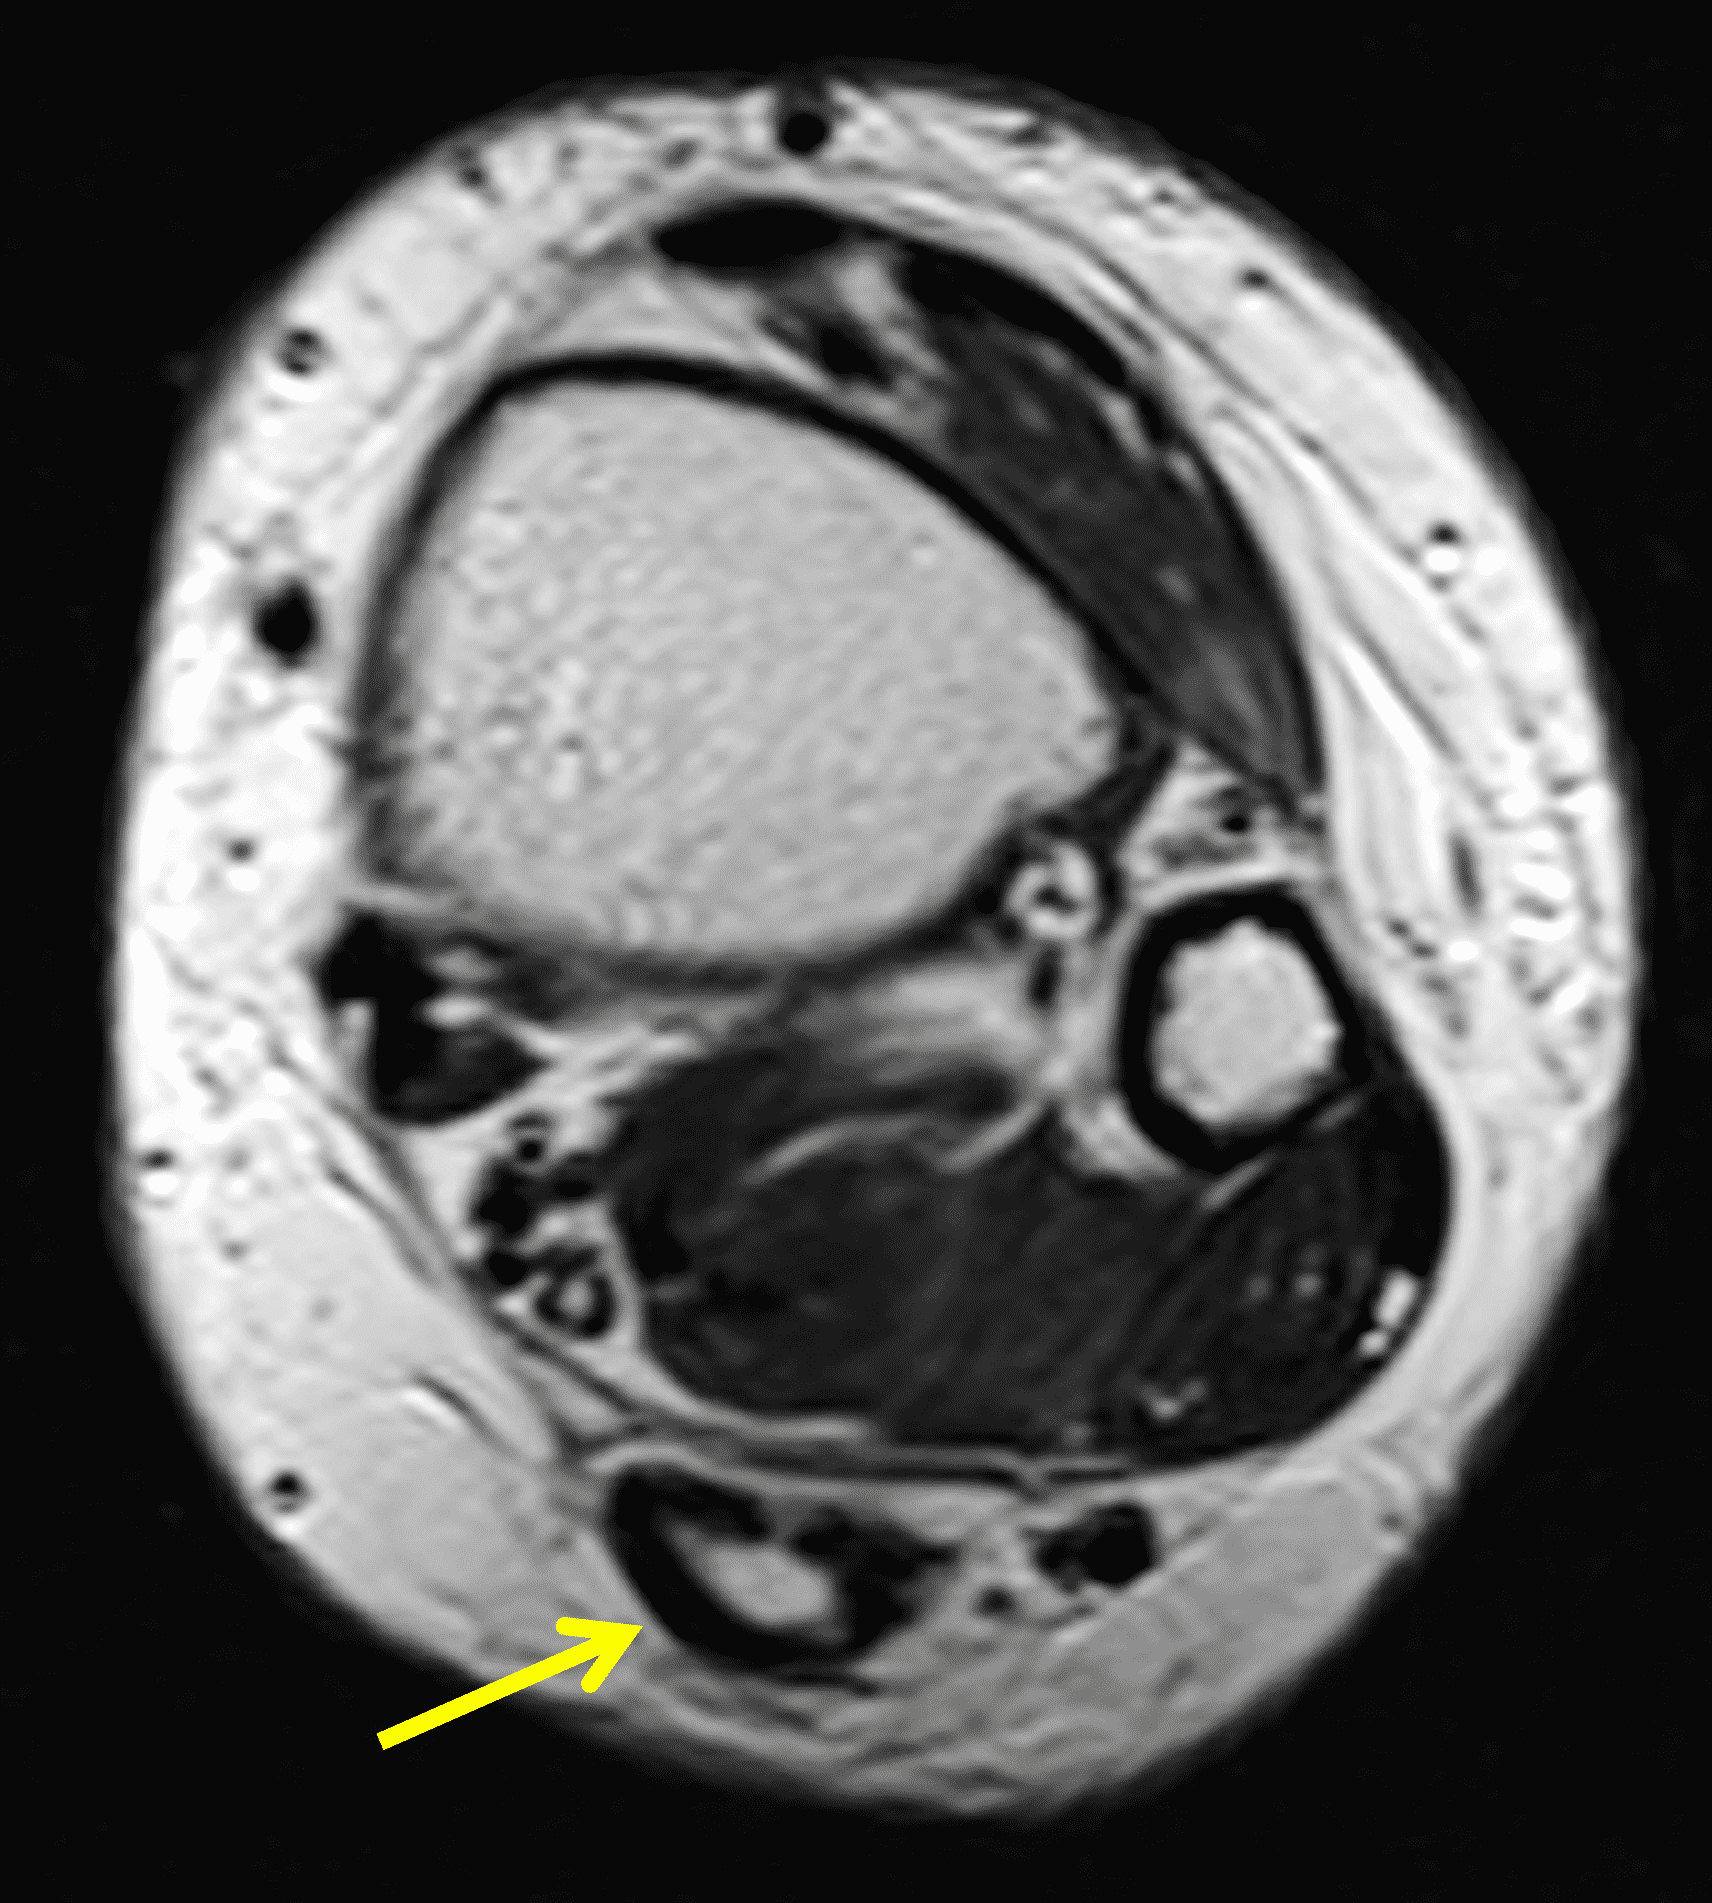

A 22 year-old male college football player presents with a “pop” and pain posterior to the right ankle during practice 1 week prior. He is unable to bear weight. Lateral radiograph (1A), sagittal fat-suppressed T2-weighted (1B), sagittal T1-weighted (1C), and transverse fat-suppressed T2-weighted images are provided. What is your diagnosis? What MRI findings affect clinical management decisions?

Figure 2: Complete Achilles tendon rupture. (2A) The lateral radiograph shows a thick and indistinct proximal Achilles tendon contour (arrows). (2B) A fat-suppressed T2-weighted image shows complete rupture of the tendon with a fluid-filled gap (yellow arrow) measuring 1.5 cm in length, located 10 cm cranial to the tendon insertion (blue arrow) and just distal to the edematous myotendinous junction (red arrow). The tear is superimposed on diffuse tendinosis. (2C) A sagittal T1-weighted image confirms the diffuse tendinosis. Fluid extends anteriorly into Kager’s fat pad (arrow) suggesting disruption of the anterior paratenon. (2D) A transverse fat-suppressed T2-weighted image through the proximal tendon shows no intact fibers (arrow), confirming the full-thickness rupture.

Acute, complete Achilles tendon rupture just distal to the myotendinous junction, superimposed on diffuse tendinosis.